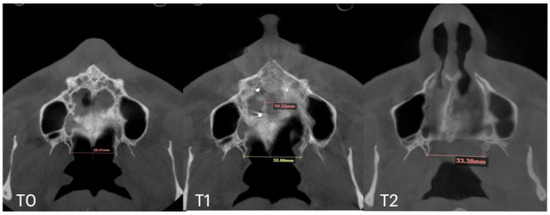

| Nasal Base Width, mm | Maxillary Base Width, mm | Lateral Nasal Width, mm | Inter-Pterygoid Distance, mm | Midpalatal Suture Separation, mm | |||||||||

|---|---|---|---|---|---|---|---|---|---|---|---|---|---|

| T0 | T1 | T2 | T0 | T1 | T2 | T0 | T1 | T2 | T0 | T1 | T2 | T1 | |

| Case A | 30.84 | 38.15 | 38.37 | 59.22 | 66.37 | 67.11 | 32.8 | 39.33 | 39.48 | 28.01 | 32.88 | 33.38 | 10.5 |

| Case B | 30.61 | 34.41 | 34.97 | 59.73 | 63.47 | 60.56 | 31.79 | 34.6 | 35.35 | 29.18 | 31.38 | 34.59 | 5.7 |

| Case C | 28.40 | 38.32 | 36.72 | 53.63 | 62.43 | 59.80 | 31.29 | 38.45 | 38.51 | 29.15 | 35.8 | 35.36 | 8.47 |

| Case D | 26.25 | 33.27 | 31.54 | 55.9 | 61.84 | 60.37 | 33.98 | 35.94 | 38.09 | 29.77 | 29.24 | 29.02 | 6.2 |